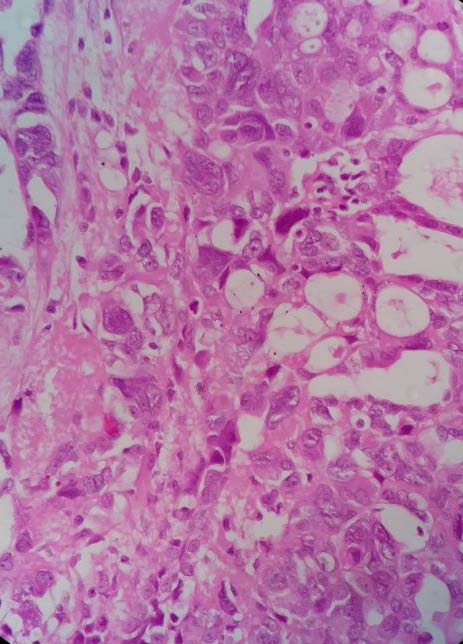

On postsurgical examination, peritoneal fluid cytology showed no evidence of malignancy. On macroscopic examination, paraovarian cyst was found to be uniloculated, filled with thin hemorrhagic fluid and a firm, greyish white nodule measuring 3x2.5x2 cm was seen in the wall of the cyst, which on cut surface was grey white, granular with large areas of necrosis. Rest of the cyst wall had smooth inner surface with foci of hemorrhages. No tumour was found in the bilateral ovaries and fallopian tubes. Microscopic examination of the right adnexal mass revealed malignant tumour with solid and tubulocystic pattern with cells lining the tubules having hobnail appearance. There was marked pleomorphism in the neoplastic cells in the solid area suggestive of high grade serous adenocarcinoma from paraovarian cyst (Fig. 1 and 2). Large areas of necrosis and stromal lymphocytic infiltration were seen. Sections of the cyst wall showed columnar to cuboidal to flattened cell lining with underlying fibrosis and infiltration by hemosiderin laden macrophages. There was no lymphovascular space invasion. Endomyometrium showed senile cystic atrophy with atrophic myometrium. Bilateral fallopian tubes and ovaries were unremarkable.